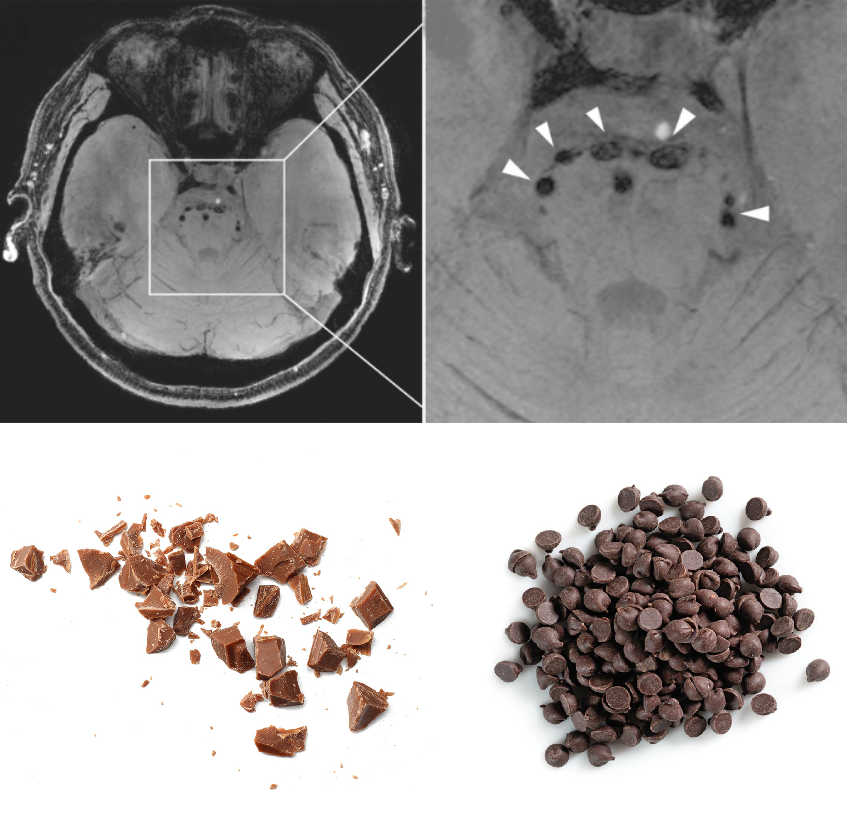

🍫«Шоколадная ΠΊΡ€ΠΎΡˆΠΊΠ°Β» Π½Π° снимкС

А Π²Ρ‹ Π·Π½Π°Π»ΠΈ, Ρ‡Ρ‚ΠΎ Π²ΠΎΠΊΡ€ΡƒΠ³ срСднСго ΠΌΠΎΠ·Π³Π° ΠΈ Π½Π° повСрхности моста Π½Π° МРВ-изобраТСниях Π² Ρ€Π΅ΠΆΠΈΠΌΠ΅ SWI ΠΌΠΎΠΆΠ½ΠΎ ΡƒΠ²ΠΈΠ΄Π΅Ρ‚ΡŒ симптом «шоколадной ΠΊΡ€ΠΎΡˆΠΊΠΈΒ»? Π­Ρ‚ΠΎ происходит Π·Π° счСт ΠΊΡ€ΡƒΠ³Π»Ρ‹Ρ… ΠΈΠ»ΠΈ ΠΎΠ²Π°Π»ΡŒΠ½Ρ‹Ρ… гипоинтСнсивных Ρ‚ΠΎΡ‡Π΅ΠΊ (β‰₯ 2 ΠΌΠΌ Π² Π΄ΠΈΠ°ΠΌΠ΅Ρ‚Ρ€Π΅), Π½Π°ΠΏΠΎΠΌΠΈΠ½Π°ΡŽΡ‰ΠΈΡ… разбросанныС ΡˆΠΎΠΊΠΎΠ»Π°Π΄Π½Ρ‹Π΅ кусочки.

πŸ“°Π”ΠΈΠ°Π³Π½ΠΎΡΡ‚ΠΈΡ‡Π΅ΡΠΊΠΈΠΉ ΠΏΡ€ΠΈΠ·Π½Π°ΠΊ описал Shoichiro Ando, экспСрт ΠΈΠ· Π˜Π½ΡΡ‚ΠΈΡ‚ΡƒΡ‚Π° исслСдований ΠΌΠΎΠ·Π³Π° УнивСрситСта Ниигаты, вмСстС с соавторами Π² Π½Π°ΡƒΡ‡Π½ΠΎΠΌ ΠΆΡƒΡ€Π½Π°Π»Π΅ ΠΏΠΎ клиничСской Π½Π΅Π²Ρ€ΠΎΠ»ΠΎΠ³ΠΈΠΈ Neurology. Π‘ ΠΏΠΎΠΌΠΎΡ‰ΡŒΡŽ Ρ‚Ρ€Π΅Ρ…ΠΌΠ΅Ρ€Π½ΠΎΠΉ рСконструкции SWI ΠΈ 7Π’ МРВ ΡƒΡ‡Π΅Π½Ρ‹Π΅ выяснили, Ρ‡Ρ‚ΠΎ эти Ρ‚ΠΎΡ‡ΠΊΠΈ ΡΠΎΠΎΡ‚Π²Π΅Ρ‚ΡΡ‚Π²ΡƒΡŽΡ‚ Ρ€Π°ΡΡˆΠΈΡ€Π΅Π½Π½Ρ‹ΠΌ экстрапарСнхиматозным сосудам.

Ряд Π°Π²Ρ‚ΠΎΡ€ΠΎΠ² ΠΏΡ€Π΅Π΄Π»Π°Π³Π°ΡŽΡ‚ ΠΈΡΠΏΠΎΠ»ΡŒΠ·ΠΎΠ²Π°Ρ‚ΡŒ симптом «шоколадной ΠΊΡ€ΠΎΡˆΠΊΠΈΒ» ΠΊΠ°ΠΊ Π½Π΅ΠΉΡ€ΠΎΠ²ΠΈΠ·ΡƒΠ°Π»ΠΈΠ·Π°Ρ†ΠΈΠΎΠ½Π½Ρ‹ΠΉ ΠΌΠ°Ρ€ΠΊΠ΅Ρ€ для HTRA1-ассоциированной Π±ΠΎΠ»Π΅Π·Π½ΠΈ ΠΌΠ΅Π»ΠΊΠΈΡ… сосудов Π³ΠΎΠ»ΠΎΠ²Π½ΠΎΠ³ΠΎ ΠΌΠΎΠ·Π³Π° (Π‘ΠœΠ‘Π“Πœ).